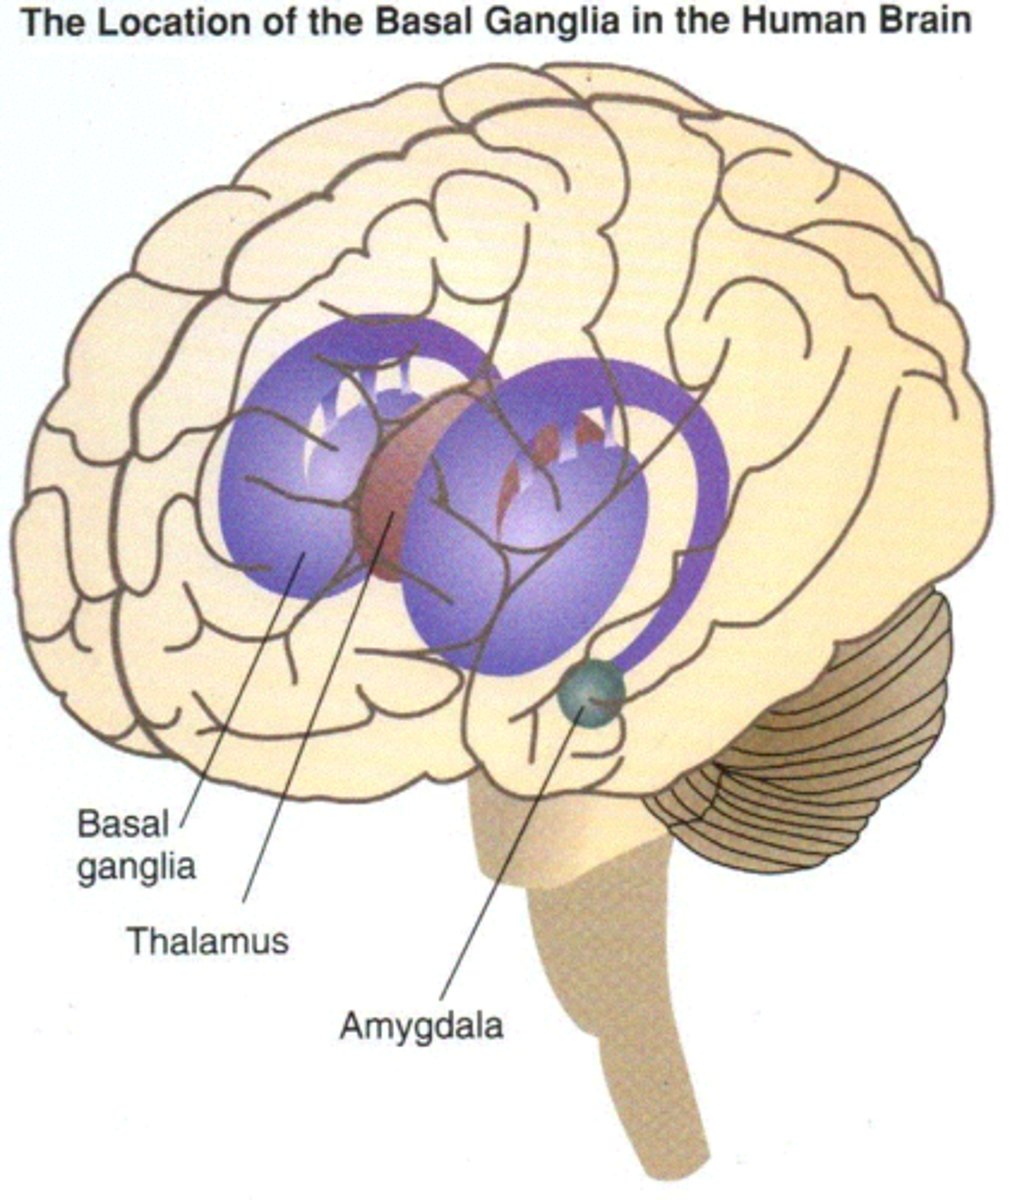

diencephalon

thalamus and hypothalamus

thalamus

relay station for all somatosensory information

intermediate mass

connection between the two thalami across the third ventricle, dumbbell shape

basal nuclei

internal masses of gray matter, smooth out motor movement